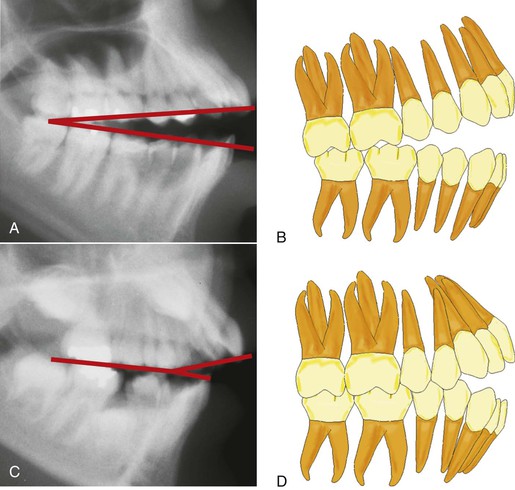

Open bite has been defined as an occlusal characteristic in which upper and lower teeth are not in contact and vertical overlap does not exist. The term was first introduced by Caravelli as early as 1842.7 Although this type of malocclusion can occur unilaterally or bilaterally in the buccal segments, it most often occurs in the anterior segment. The anterior open-bite malocclusion is most obvious when a clearance is apparent between the upper and lower incisors from the frontal view. Of course, clinical diagnosis of an anterior open bite then becomes somewhat subjective because the diagnosis depends on the horizontal plane of assessment (Fig. 9-1).

Figure 9-1 Evaluation of an anterior open bite from different planes. A, Minimal amount of anterior open bite is evident from the uppermost view angle. B, Increased open bite compared to A. Plane of assessment is almost perpendicular to the occlusal plane. C, The lowermost view angle reflects an extensive open bite, one that does not appear as extensive from the top view. The apparent magnitude of the open bite depends on the steepness of the occlusal plane and/or the plane of evaluation.